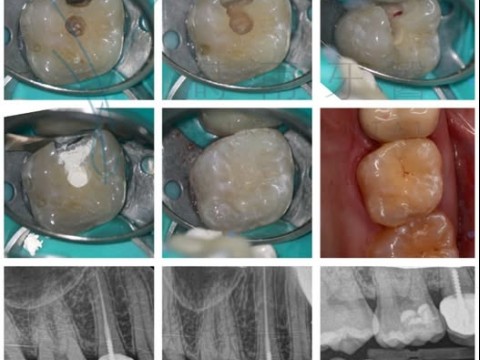

拯救牙齒 避免根管治療 – 活髓保存術

什麼是活髓保存術? 過去一旦牙髓腔暴露於口腔環境中,為了避免無法預知的感染後患,往往只能進行根管治療(抽神經),將牙髓腔內所有組織斬草除根,以免細菌死灰復燃,但牙髓腔內的組織是供應養分的主要來源,也是牙齒...